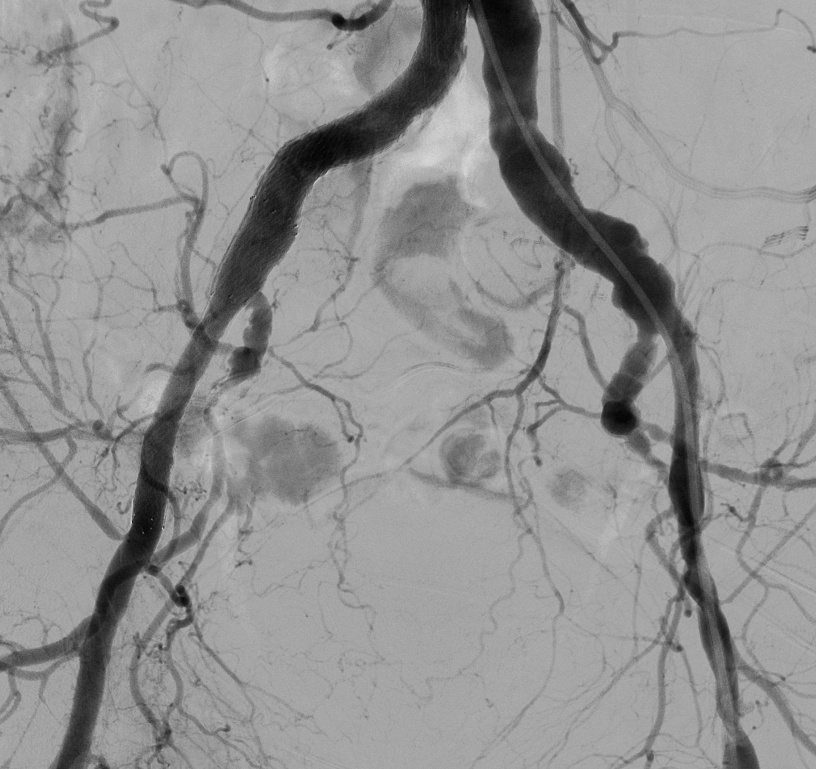

— Вчера мы с Виктором Анатольевичем Егоровым сделали показательную операцию, — рассказывает заведующий отделением рентгенэндоваскулярных методов диагностики и лечения Павел Антонович Алимов. — У пациента была патология терминального отдела аорты с преимущественным поражением левой подвздошной артерии. Поставили один стент. Всё.

За этой краткостью — огромный путь, который прошла сосудистая хирургия. Ещё недавно такому пациенту делали бы полостную операцию: долгий наркоз, большой разрез, недели в стационаре, месяцы реабилитации. Риск осложнений, тяжёлое послеоперационное восстановление.

— Сегодня мы можем сделать то же самое эндоваскулярно, — поясняет Алимов. — Это гораздо менее травматично, не требует сложного анестезиологического пособия, а восстановительный период — в разы короче.

В сосудистом отделении СМЦ ФМБА России выполняют как открытые операции на терминальном отделе аорты, так и эндоваскулярные вмешательства. В том числе при синдроме Лериша — тяжёлой патологии, когда сужение аорты грозит ампутацией конечностей.

Исследования подтверждают: эндоваскулярное лечение аорто-подвздошных окклюзий демонстрирует технический успех до 97,8%, а средний срок госпитализации составляет всего 2 дня. При открытых операциях эти цифры совершенно иные.